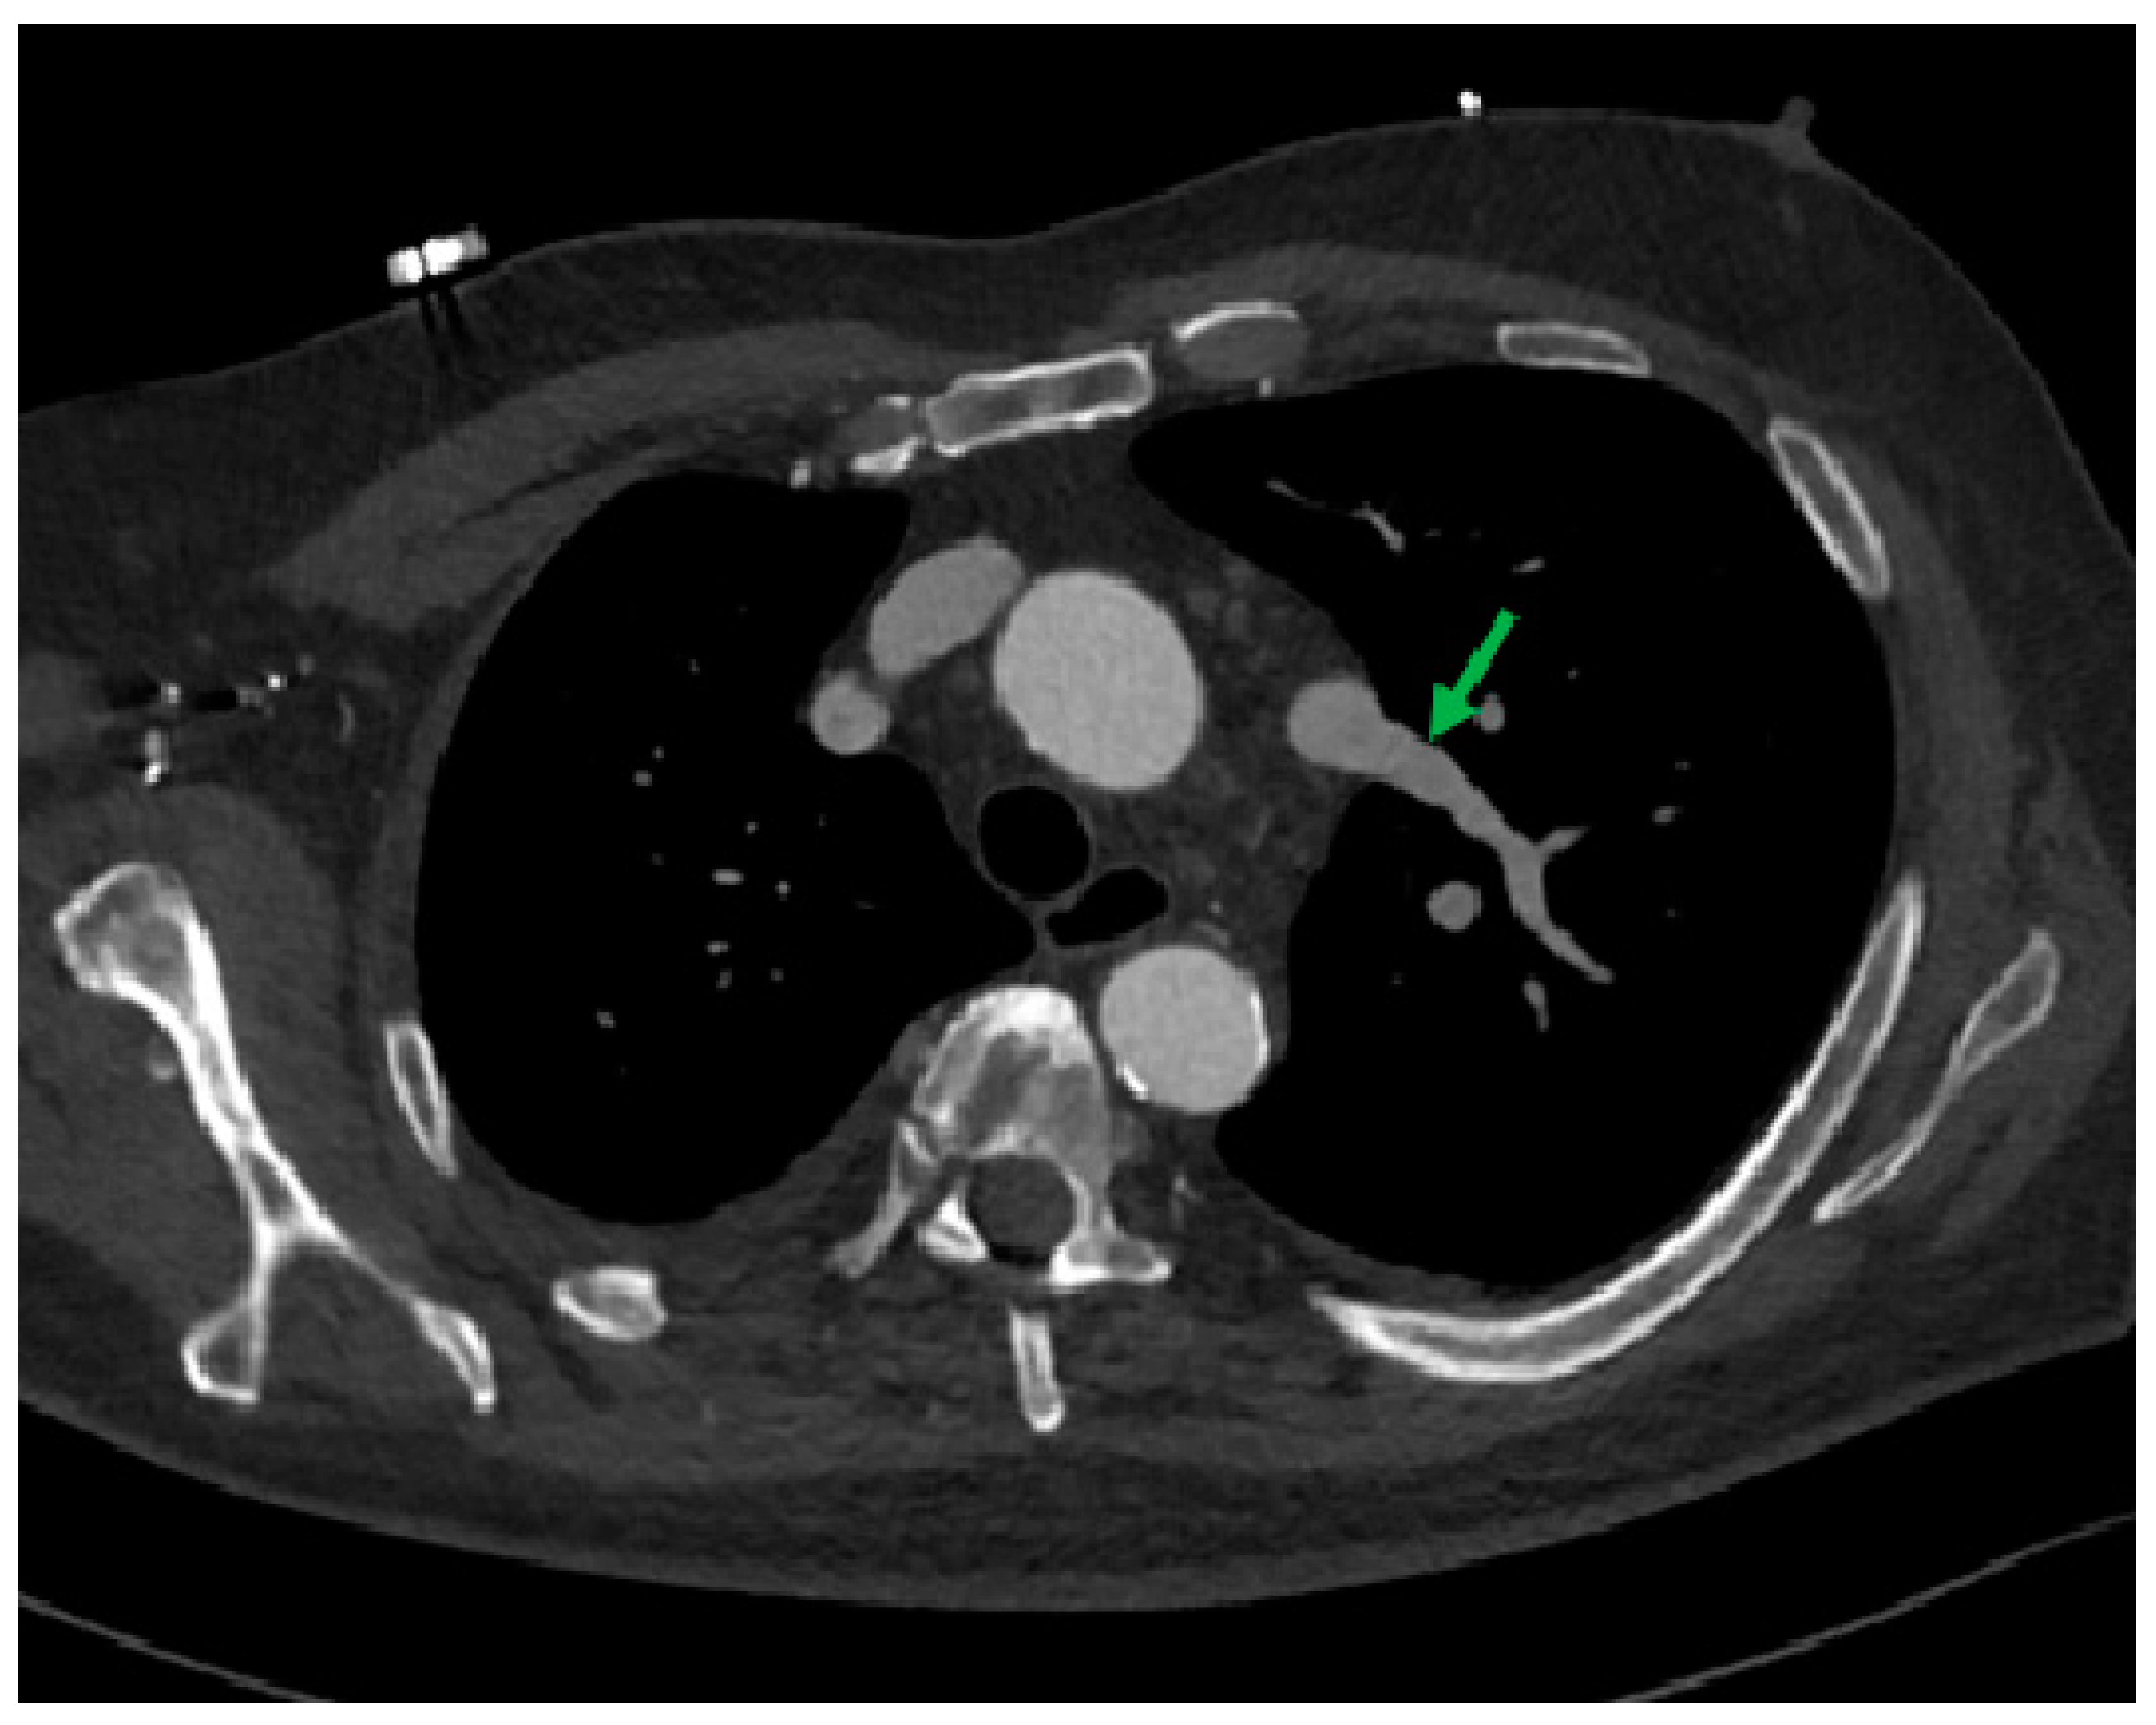

- Incidental vascular finding No. 4: Left Superior Pulmonary Vein Draining into Left Brachiocephalic Vein.